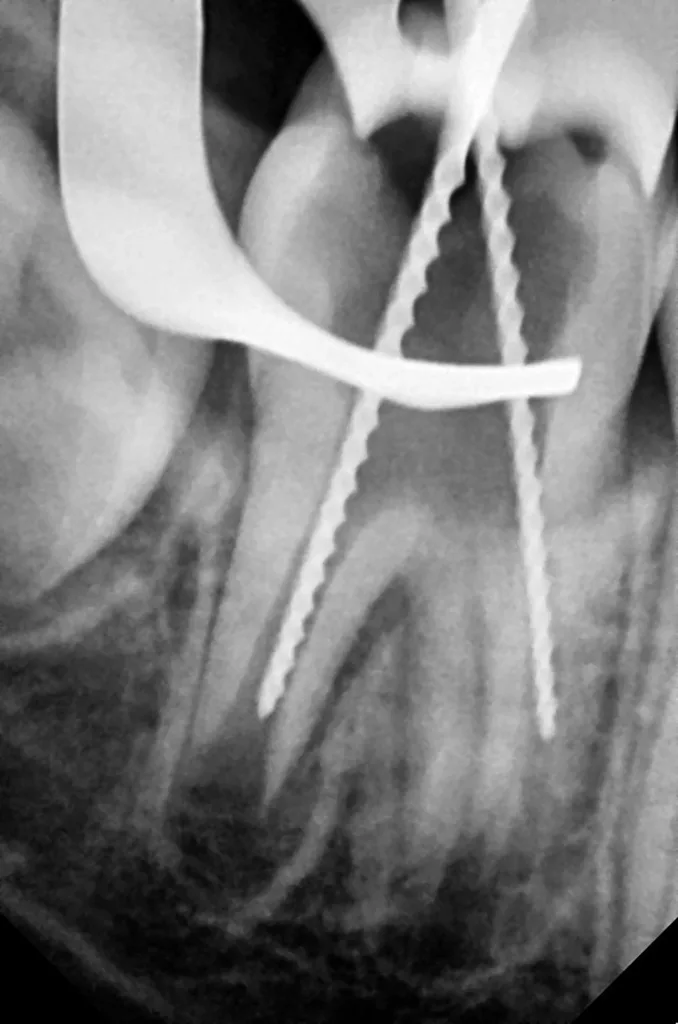

Der elfjährige Junge stellte sich aufgrund starker, anhaltender Schmerzen in regio 47 vor. Der Zahn 47 war gerade im Durchbruch und noch mit einer nichtentzündeten Zahnfleischkapuze partiell überdeckt (Abb. 61). Die Schleimhaut bereitete bei der Palpation keine Schmerzen. Die Perkussion des Zahnes 47 selbst war jedoch positiv. Das Röntgenbild zeigte unter dem komplett erhaltenen Zahnschmelzmantel einen umfangreichen runden Dentindefekt, der fast bis zum Pulpakavum reichte. Der kortikale Knochen der Wachstumszone war praktisch nicht verändert, es war jedoch eine Erweiterung des Parodontalspaltes zu beobachten (Abb. 62). Aufgrund der vorliegenden klinischen und radiologischen Befunde wurde vorläufig eine PEIR des Zahnes 46 (Grad 3 der Läsion nach Seow) diagnostiziert, die durch eine akute Pulpitis verkompliziert wurde. Der Patient und seine Mutter wurden ausführlich über die Behandlungsmöglichkeiten aufgeklärt. Aufgrund der Komplexität des Falles und der Angst des Patienten erfolgte die Behandlung in ITN.

Nach chirurgischer Freilegung mit dem Khors Koagulator (ЭСТАТЕХ, Ukraine) (Abb. 63) wurde mithilfe der Klammer Nr. 51 (KSK DENTECH, Japan) Kofferdam gelegt (Abb. 64). Die Verbindung zur Läsion hatte lediglich einen Durchmesser von ca. 1 mm und war gut visualisierbar (Abb. 63 und 64). Das Innere des Läsionskörpers war hohl und enthielt schwarze Reste nekrotischen Gewebes am Dentin, das leicht mit einem Rosenbohrer entfernt werden konnte. Die Pulpa war bereits beteiligt und sah komplett nekrotisch aus (Abb. 65). In diesem Fall kam eine Vitalerhaltung der Zahnpulpa nicht infrage, und somit wurde die Indikation für eine Wurzelkanalbehandlung gestellt. Für die Wurzelkanalaufbereitung wurde eine H-File (Mani, Japan) in der ISO-Größe 80 verwendet und die Kanäle wurden mit 3%igem NaOCl unter Ultraschallaktivierung gespült (Abb. 66). Wegen des starken apikalen Exsudats konnten die Wurzeln nicht sofort mit einer definitiven Füllung verschlossen werden. Aus diesem Grunde wurde nach einer Spülung mit 17%iger EDTA zunächst eine Kalziumhydroxidpaste (UltraCal XS, Ultradent, USA) als medikamentöse Einlage in die Wurzelkanäle eingebracht und der Zahn temporär adhäsiv verschlossen (Abb. 67). Während des zweimonatigen Beobachtungszeitraumes berichtete der Patient über durchgehende Beschwerdefreiheit und Symptomlosigkeit. Der Zahn war weiter durchgebrochen, und der junge Patient zeigte sich nun kooperativ, sodass die Behandlung ohne Sedierung fortgesetzt werden konnte. Die temporäre Kompositfüllung war intakt (Abb. 68), und auf einem neu angefertigten Röntgenbild erschien der zuvor deutlich erweiterte Parodontalspalt sichtbar verkleinert (Abb. 69).